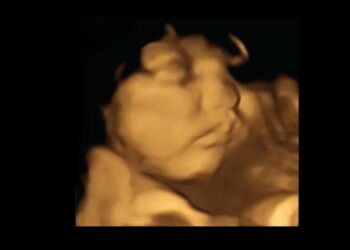

Studie belegt: Kinder im Mutterleib erkennen bereits Gesichter von Johann R. Porter 5 Januar, 2021 0 1.2k Eine Studie beweist die vorgeburtliche Veranlagung zur Erkennung von Menschen. Hinweis auf bereits hohen Entwicklungsstand vorgeburtlichen Lebens.